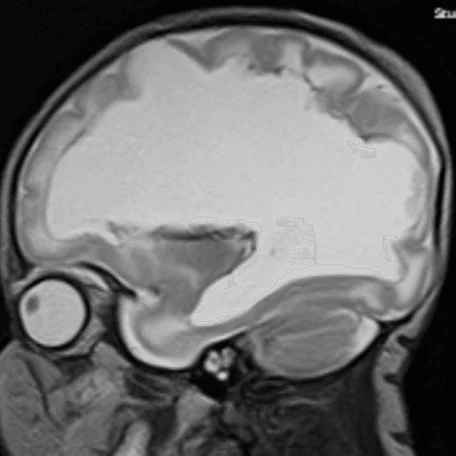

Внутрижелудочковые кровоизлияния

Чаще возникают у недоношенных новорожденных. Основным источников ВЖК служат сосуды эпендимы мозга и сосудистые сплетения. Способствующие факторы: затяжные или быстрые роды, перинатальная гипоксия, коагулопатии, нестабильность гемодинамики у новорожденного.